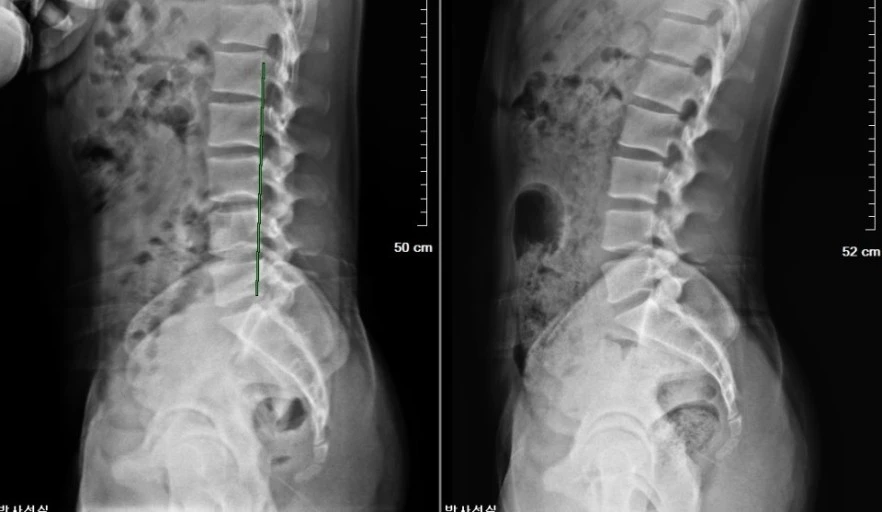

(왼쪽) 일자 허리 (오른쪽) 정상 C자 허리

허리를 삐면 허리 주변의 근육들이 놀라서 수축을 한다. C자형이어야 하는 척추가 수축을 한 근육이 척추를 확 당겨서 일자가 된다. 그래서 허리가 뒤로 구부려지지 않았고, 척추가 참 반듯하게 서있었다. 거울로 옆모습을 보면 허리가 정말 일자로 보였다.